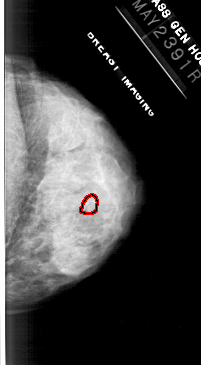

A_1113_1.RIGHT_CC

RIGHT_CC LINES 4741 PIXELS_PER_LINE 2611 BITS_PER_PIXEL 12 RESOLUTION 43.5 OVERLAY

FILE: A_1113_1.RIGHT_CC.OVERLAY

TOTAL_ABNORMALITIES 1

ABNORMALITY 1

LESION_TYPE CALCIFICATION TYPE PLEOMORPHIC DISTRIBUTION CLUSTERED

ASSESSMENT 4

SUBTLETY 3

PATHOLOGY MALIGNANT

TOTAL_OUTLINES 1

BOUNDARY